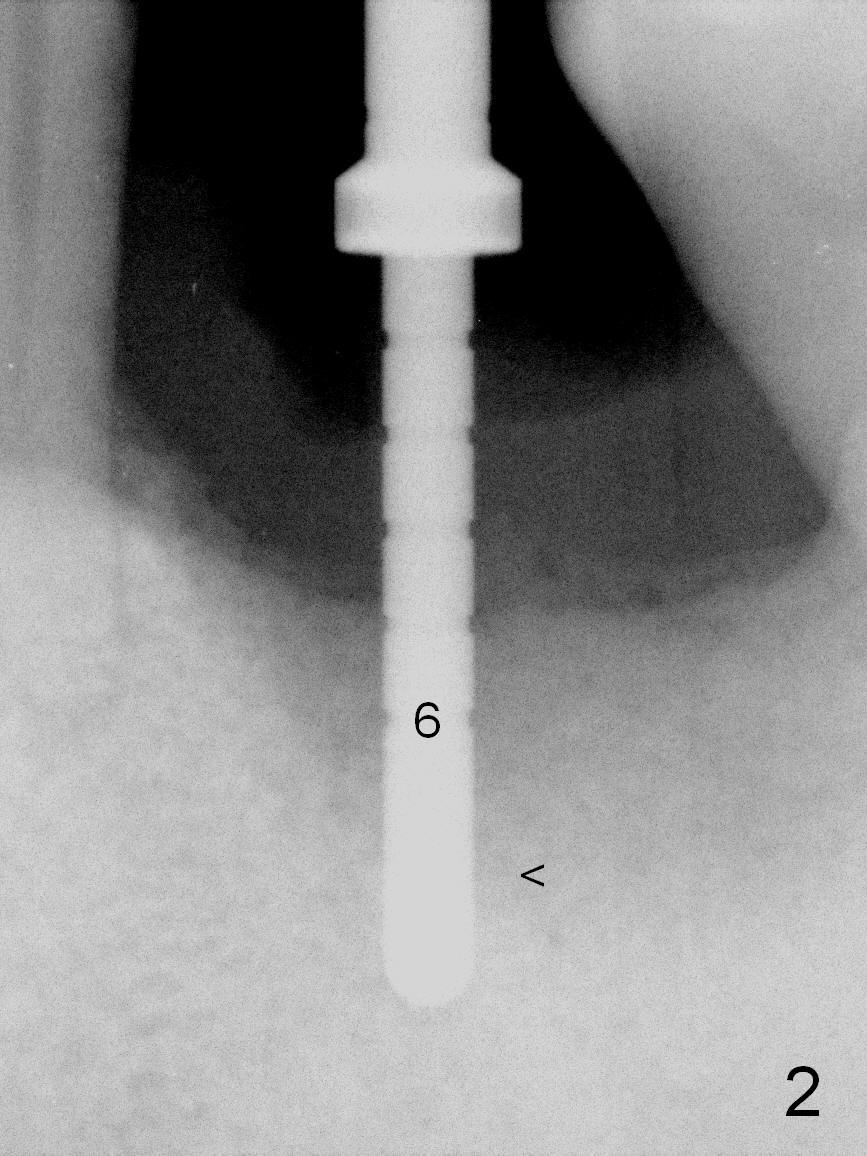

When the patient returns for #19 extraction and immediate implant, there is buccal (Fig.1 *) and lingual gingival swelling. The distobuccal root is exposed (D). Both the buccal and lingual walls are low. There is no septum. After removal of granulation tissue, an osteotomy is established in the bottom of the socket (slightly mesiolingually). The depth is approximately 3 mm in new bone (half of 6 mm and arrowhead). When the depth increases approximately 6 mm in new bone (Fig.3 arrowhead with 6x20 mm tap (T) in place), the Inferior Alveolar Canal is still invisible in PA. Panoramic X-ray has to be taken (Fig.4). So far infiltration anesthesia has been administered. When #2 sensor is inserted in the lingual vestibule, the patient feels pain and nausea. Lingual Nerve block is provided. The patient feels pain when further osteotomy is carried on. Since the depth of the osteotomy is confirmed by panoramic X-ray, Inferior Alveolar Nerve block is added. A 6x17 mm tissue-level implant is placed with clearance from the Inferior Alveolar Canal (Fig.5: red dashed line: the superior border of the Canal). Therefore, Lingual Nerve block allows lower placement of sensor so that the Inferior Alveolar Canal is detectable by PA.

The implant is placed lower by 1 thread (compare arrowheads in Fig.5,6). Bone graft (Fig.6 *) and Osteoplug are placed in the remaining socket (mainly mesiobuccodistally). An abutment (A) is placed for immediate provisional.